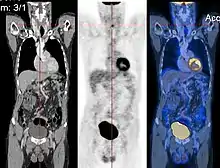

Registration

Image registration is a process that searches for the correct alignment of images.[21][22][23][24] In the simplest case, two images are aligned. Typically, one image is treated as the target image and the other is treated as a source image; the source image is transformed to match the target image. The optimization procedure updates the transformation of the source image based on a similarity value that evaluates the current quality of the alignment. This iterative procedure is repeated until a (local) optimum is found. An example is the registration of CT and PET images to combine structural and metabolic information (see figure).

- Combining complementary information from different imaging modalities. An example is the fusion of anatomical and functional information. Since the size and shape of structures vary across modalities, it is more challenging to evaluate the alignment quality. This has led to the use of similarity measures such as mutual information.[25]